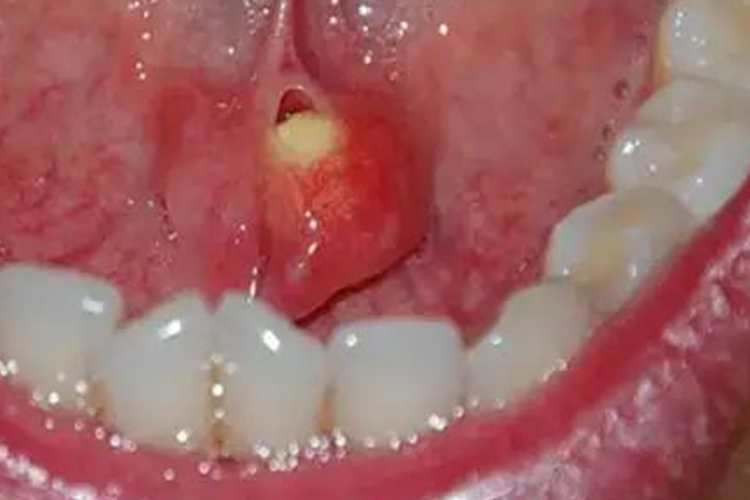

唾液腺结石较小时可能没有任何的临床症状。在导管内的结石发生阻塞时,可出现进食时腺体肿大,患者自觉肿胀、疼痛。停止进食后不久腺体自行复原,疼痛亦随之消失。部分患者腺体肿胀可持数小时、数天,甚至不能完全消退。患者的导管口黏膜红肿,挤压腺体可见少量脓性分泌物自导管口溢出。

典型的唾液腺结石为长圆形,呈枣核状,小的如米粒大小。